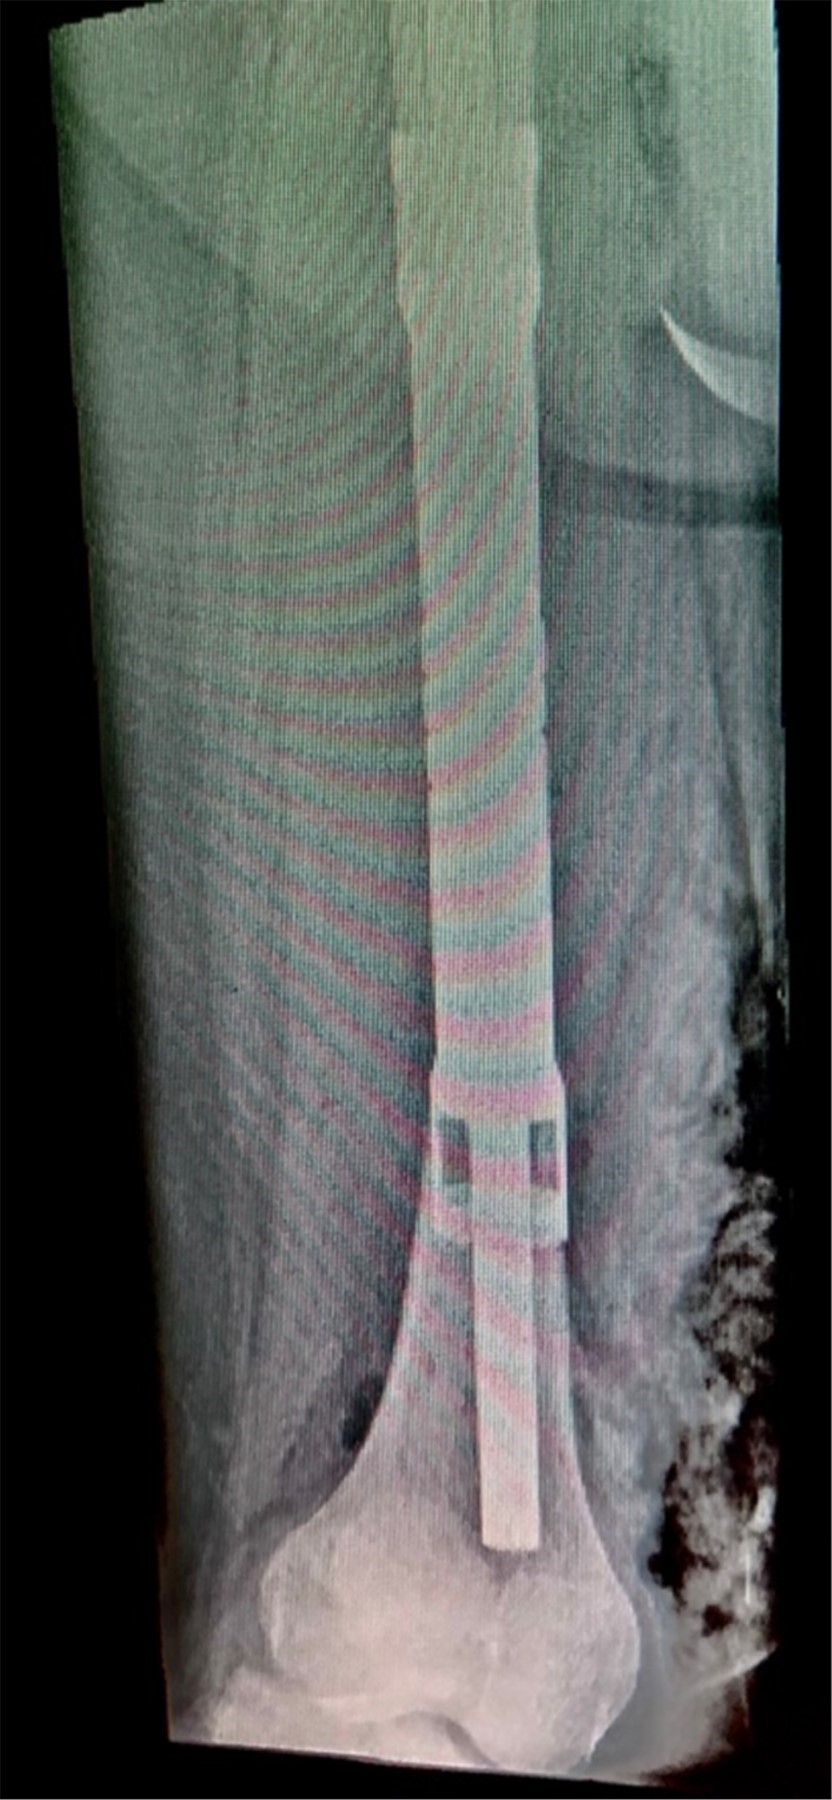

Con la paciente bajo anestesia general y en decúbito supino, se realiza asepsia, antisepsia y colocación de campos quirúrgicos estériles. Se opta por un abordaje anteromedial de fémur, mediante incisión longitudinal de aproximadamente 25 cm, disecando por planos hasta encontrar intervalo entre músculos recto femoral y vasto medial; después se encuentra el vasto intermedio, el cual se diseca hasta encontrar diáfisis femoral. Se observa tumoración en tercio medio de diáfisis femoral de aproximadamente 13 cm de longitud por 3 cm de ancho, el cual se reseca con bordes amplios, realizando osteotomía a 16 cm proximales de superficie articular de la rodilla (Figura 3); se envía muestra medular transquirúrgica, recibiendo confirmación de presencia de bordes libres por el Servicio de Patología. Se realiza segunda osteotomía a 16 cm distales del trocánter mayor, se envía segunda muestra de médula ósea, recibiendo reporte negativo para células malignas. Se realiza rimado de fémur proximal y distal con rimas diámetros 9, 10 y 10.5 hasta atravesar fosa digital proximalmente; se coloca asentador para hueso, regularizando el límite de la osteotomía. Se introduce clavo endomedular hasta limite distal establecido (Figuras 4 y 5) y se coloca prótesis diafisaria (Figura 6) con asentadores y coronas en extremos diafisarios, respectivamente. Se procede a colocar pernos de bloqueo, verificándose longitud de extremidad (Figura 7) comparando con la contralateral. Se repara intervalo entre recto femoral y vasto medial y se procede a cierre por planos.

Figura 4

Figura 5